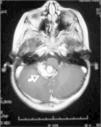

A los 4 años, ante un empeoramiento de la inclinación de la cabeza y aparición de cierre parcial del ojo derecho, es reevaluada por oftalmología, donde se le diagnostica una hiperfunción del músculo oblicuo inferior derecho. Por ello, se la remite de nuevo a neurología, donde le indican una resonancia magnética (RM) craneal, en la que se evidencia una tumoración de 2cm, de origen en pedúnculo cerebeloso derecho (fig. 1).